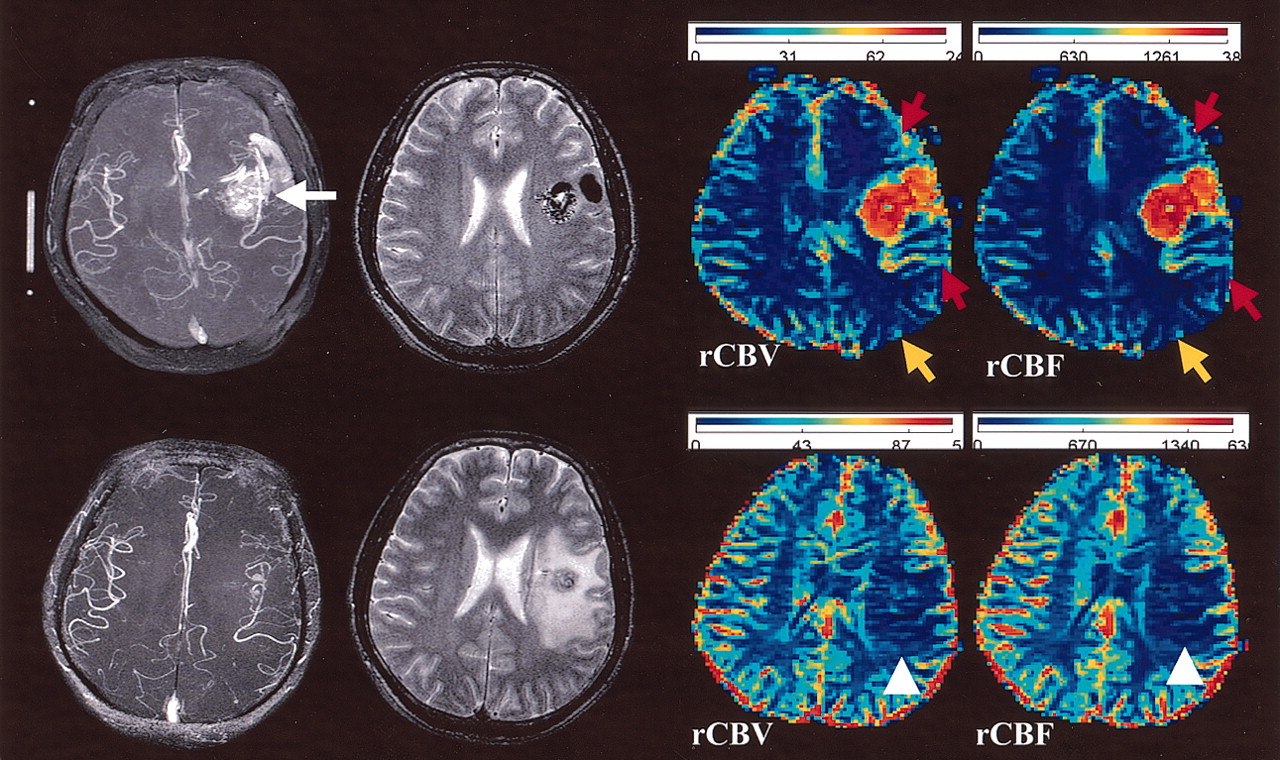

Composite images in case 3.

Upper row (before radiosurgery), Collapsed-view 3D time-of-flight MR angiogram shows a left temporal lobe AVM (white arrow). T2-weighted transaxial image shows the AVM. Perfusion maps show increased rCBV and rCBF in the immediate anterior and posterior areas (red arrows), and decreased rCBV and rCBF in the posterior remote area (yellow arrow), indicating type 2 perfusion disturbance.

Lower row (24 months after radiosurgery), Collapsed-view 3D time-of-flight MR angiogram shows a small remnant of the AVM. T2-weighted transaxial image shows a moderate degree of radiation-induced edema. Perfusion maps show decreased rCBV and rCBF in the perinidal regions (arrowheads). They correspond to the regions with radiation-induced edema.